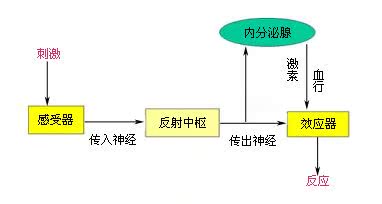

3.神经调节障碍:

唾液分泌的调节完全是神经反射性的,当神经调节发生障碍,就会出现睡觉时流口水的情况。